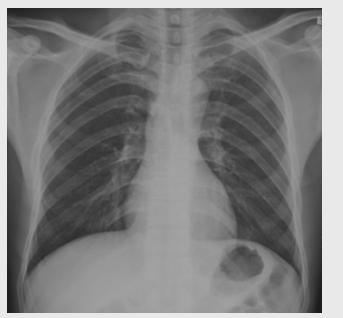

01卷-3.根據(jù)下圖請做出正確診斷

A.正常心臟

B.心肌病(普大心)

C.風(fēng)濕性心臟病(梨型心)

D.主動脈型心(靴型心)